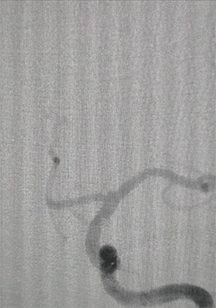

现病史:8月前,患者因头痛1年,发现颅内动脉瘤半月入院,DSA造影显示左侧颈内后交通动脉瘤及左侧颈内动脉分叉部动脉瘤,考虑到患者经济状况,决定先行Solitaire支架下弹簧圈栓塞治疗位于左侧颈内动脉后交通段动脉瘤,支架自大脑中动脉M1放至颈内动脉近端。手术顺利,患者病情平稳后出院。术后8月余,行二期治疗,支架下弹簧圈栓塞左侧颈内动脉分叉部动脉瘤。

颅脑DSA

临床诊断:左侧颈内动脉分叉部宽颈动脉瘤;左侧颈内动脉后交通动脉瘤支架辅助栓塞术后。

动脉瘤尺寸:2.7*2.1mm

患者动脉瘤位于颈内动脉分叉部,部分瘤颈累及A1;动脉瘤破裂出血的风险相对较高,需要手术干预。该动脉瘤属宽颈,单纯弹簧圈栓塞,弹簧圈易脱出,需支架辅助栓塞。病人选择支架下弹簧圈栓塞治疗技术。

患者一期使用Solitaire支架治疗同侧颈内交通段动脉瘤,且支架远端落点位于M1段。根据前期治疗情况,有两种支架释放方案: